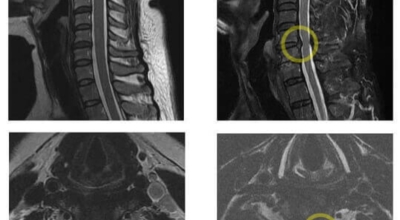

목디스크 증상이 나타날때 빨리 발견하여 비수술 치료를 받고 꾸준히 관리하는 것이 베스트이죠. 목디스크 환자 중 수술을 진행하는 환자는 2% 미만으로 현저히 적다고 해요. 수술을 진행하는 경우는 감각이 느껴지지 않는 마미증후군이나, 한쪽 다리가 눈에 띌 정도로 야윈 경우에만 진행하므로 올바른 자세 교정만으로도 충분히 호전될 수 있는 질병이죠. 목에 연관된 검사는 MRI나 CT를 이용해요. 그러나 전자의 경우 비용이 굉장히 비싸기 때문에 디스크 증세가 확실하다고 생각될 경우에만 선택적으로 하고 의무적으로 하는 건 아니니까 비용에 대해선 부담을 가지지 마시길 바래요.

목디스크 증상으로 인해 3개월 이상 약물이나 물리치료를 해도 효과가 없을 경우 수술을 고려해야 해요. 통증이 심해서 일상생활에 지장이 있거나, 신경증상이 악화되고 근력도 함께 줄어들 때와 큰 디스크가 탈출해 중추신경인 척수를 압박해 척수증이 발생하는 경우에도 수술을 고려할 수 있어요.